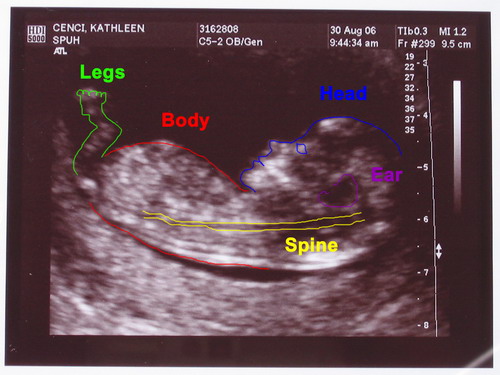

| On August 30, 2006 we had the first sonogram. This was the first photo we received. As you'll see I attempted labeling roughly where the parts are. Also if you want to see a much larger version (4mp, screen size or bigger) click on either image to see it. |

Click on any/all of the photos above to see more. The links will give you full resolution photos (4mp) and labeled versions. The labeling is my best guess as to what your looking at. We saw much more on the monitor, the motion version was awesome. In one instance the babys arm was in view and it was wiggling around. It almost appeared to be waving to us, it was amazing.